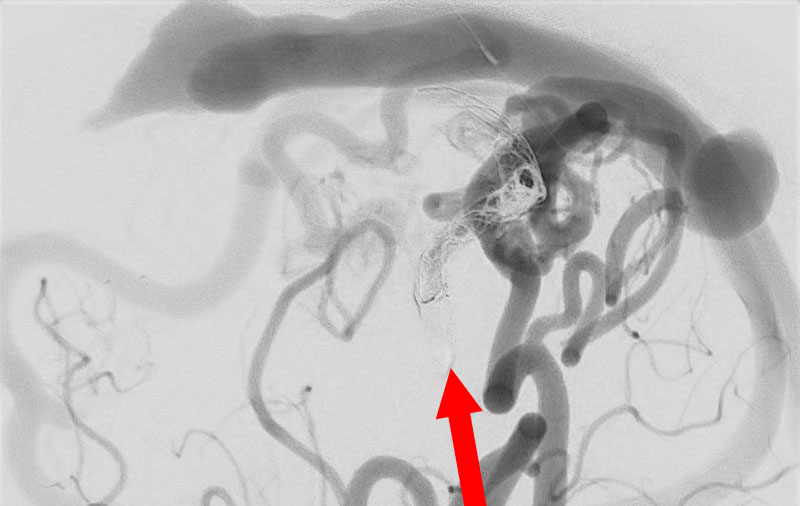

No.1620 手術前

No.1620 手術中

No.1620 手術後

'26年3月

出血性脳動静脈奇形

10代

院内外来